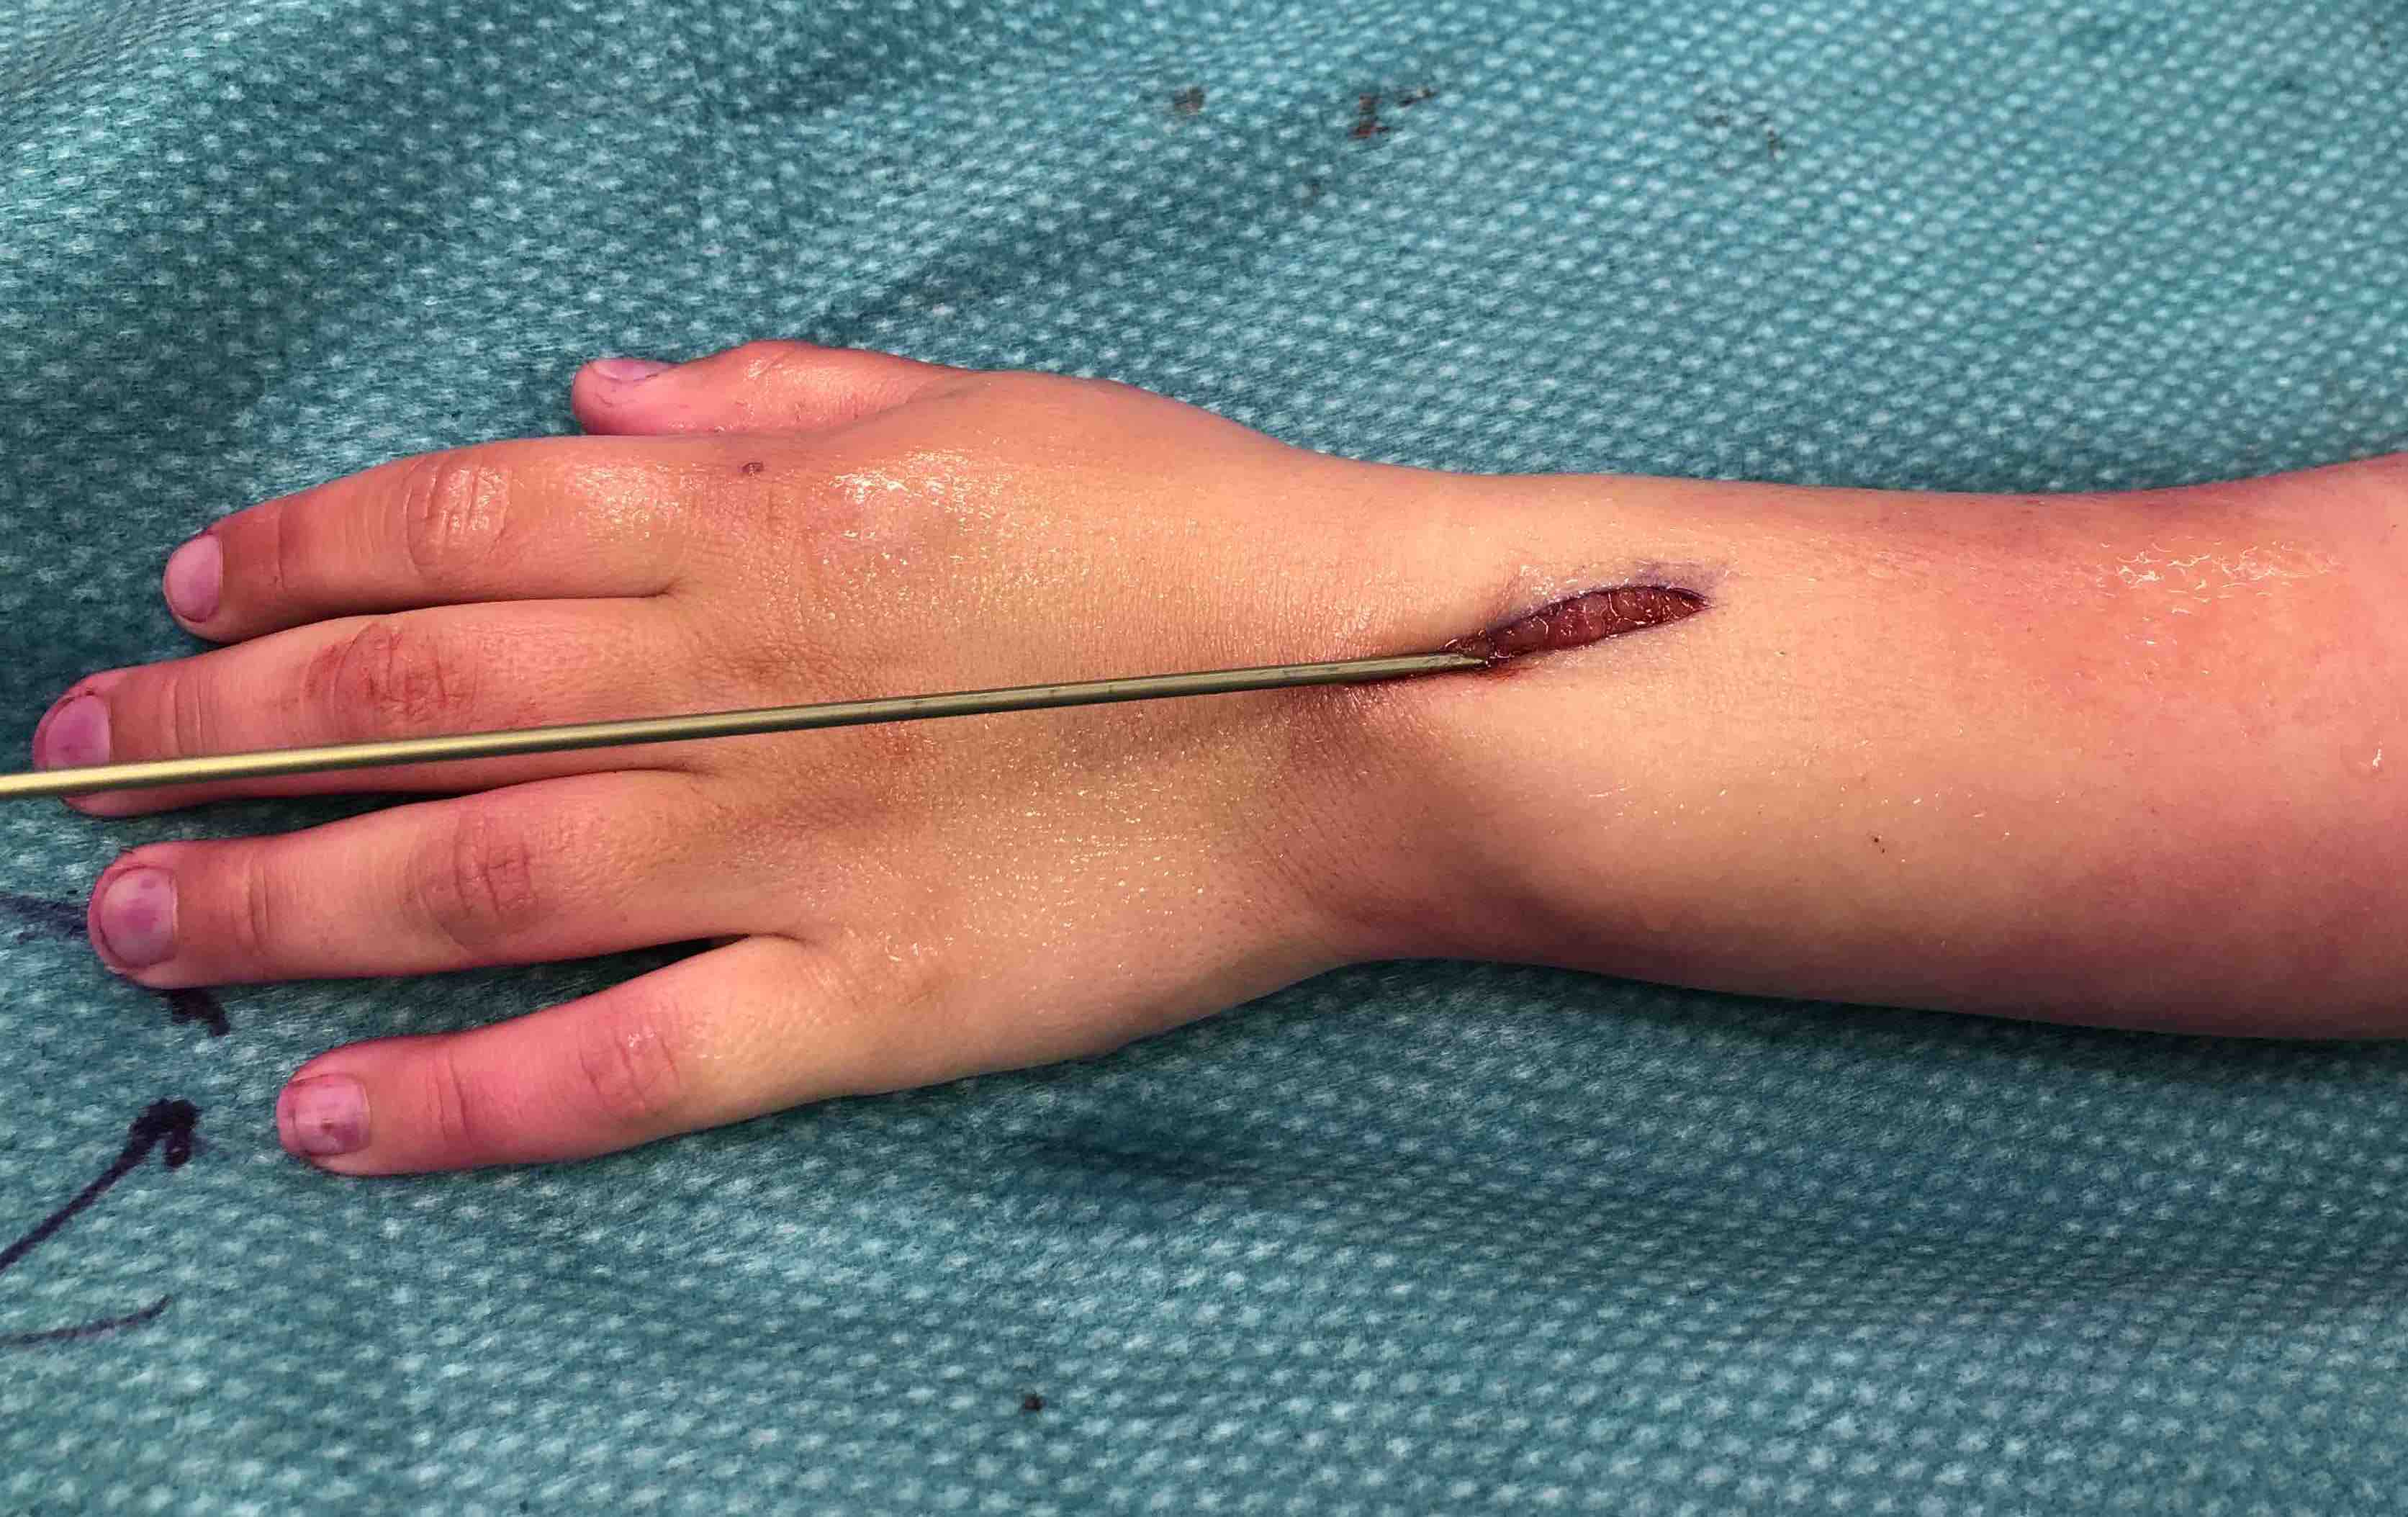

- risk of extensor tendon rupture due to prominence of nails at insertion sites

TENS technique

Technique

Radius (typically first as more difficult to reduce)

Entry point with awl 2 cm proximal to distal physis

1. Radial styloid / distal lateral entry

- ensure radial nerve / cephalic vein, 1st extensor compartment protected

2. Listers tubercle / dorsal entry

Cut nail

Withdraw 1 cm, cut with endcutter, then advance

Extensor tendon injuries with elastic nails

- 202 elastic nails

- 3/202 (1.5%) EPL ruptures

Murphy et al J Pediatr Orthop 2019

- systematic review of 33 EPL ruptures post elastic nail

- all with dorsal approach to the radius

- average 10 weeks post surgery

- treated with repair, EIP to EPL transfer, or graft reconstruction with palmeris longus